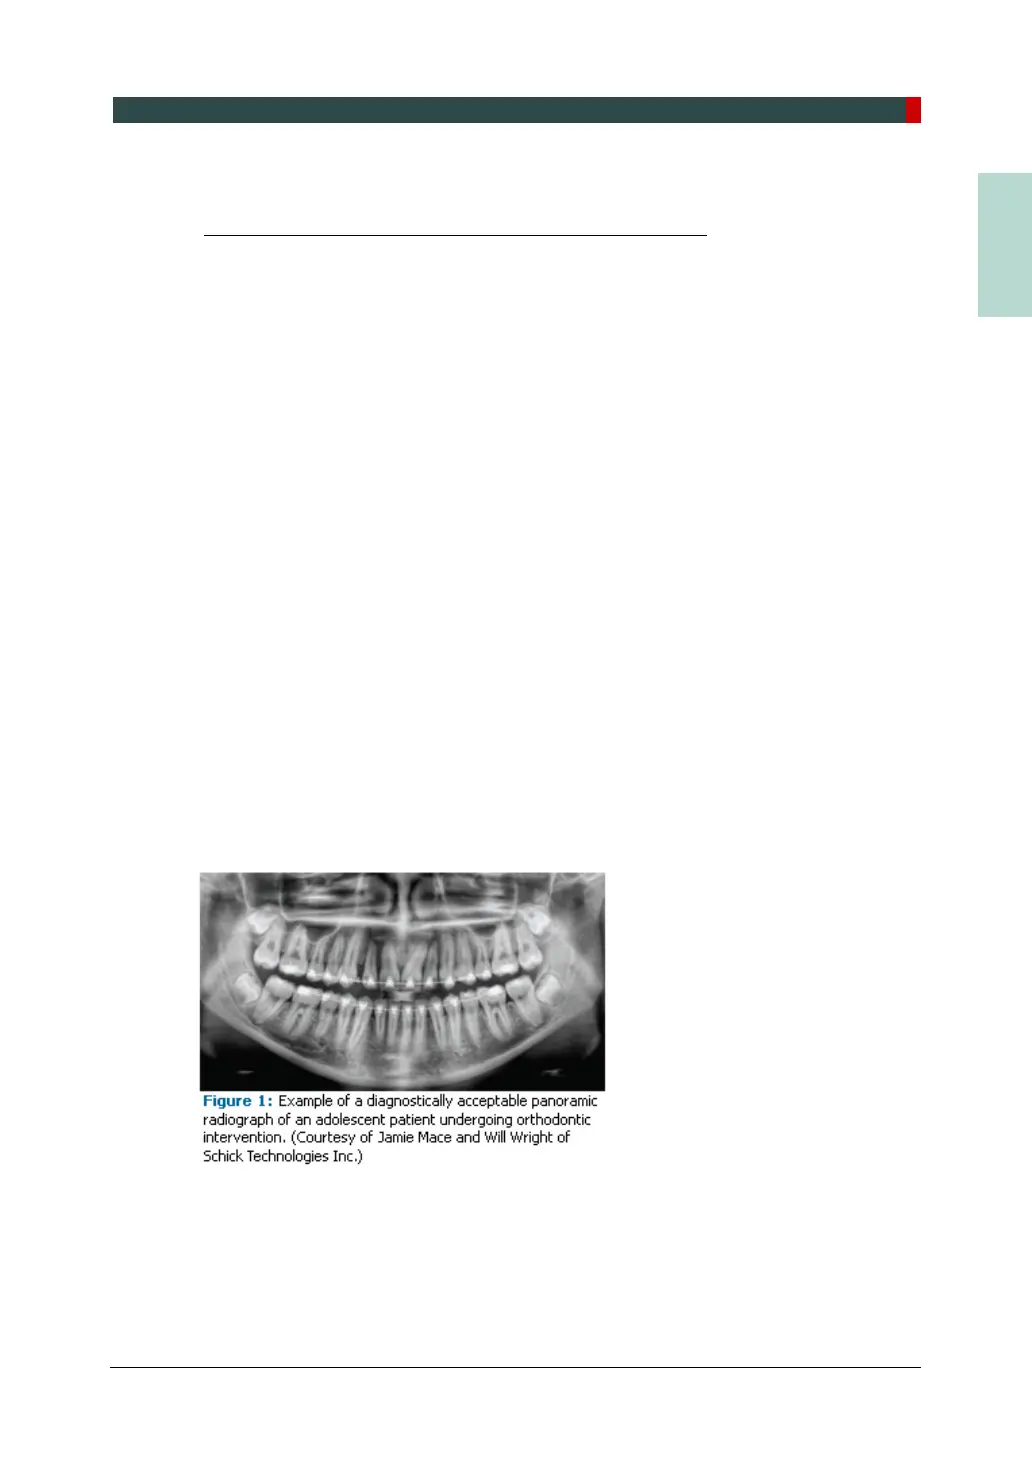

A quality panoramic radiograph should image all of the teeth, erupted and unerupted, in

both the maxillary and mandibular arches from condyle to condyle in the horizontal

dimension, and from the superior third of the orbit in the superior region to the inferior

border of the mandible in the inferior region.

8,9

The arches should appear straight or

slightly U-shaped with the occlusal plane parallel to the horizontal edges of the film

(Figure 1). The anterior teeth must not be magnified or diminished in size, and the

overlapping of adjacent posterior teeth should be kept to a minimum.